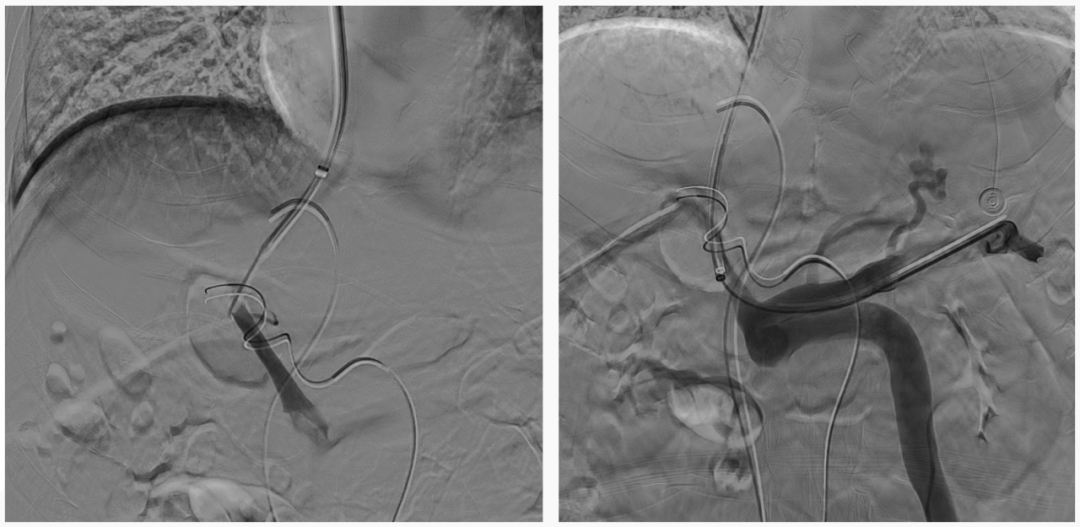

异常分流道栓塞后,再次行门静脉造影,血流呈向肝状态,食管胃底曲张静脉较前更显著,微导管超选至曲张的胃冠状静脉,予以弹簧圈及25%生物胶栓塞,造影示曲张静脉消失,肝内门脉显影较术前显著改善

仔细评估术前CT可知,该患者的异常分流道的出口并不引流至肾上腺静脉,故难以通过常规BRTO途径栓塞,因而对于该患者团队仔细评估后决定采用TIPS联合异常分流道近端栓塞的方法。既往对于此类粗大分流道,无论是单纯使用可控弹簧圈或是弹簧圈联合组织胶水都存在栓塞效率或是安全性的不足,该患者使用血管塞封堵减缓血流后,在血管塞细密的网孔阻隔下能够有效防止补充栓塞的组织胶逃逸,进而获得良好的栓塞效果及效率。

术后患者的肝脏血管超声提示患者原本的离肝血流已逆转为向肝血流,1月后的CT复查显示门静脉较术前的纤细状态已得到明显恢复,间接证实TIPS分流并未进一步降低患者的肝脏灌注,其随访至今也未在发生肝性脑病。对于自发性门体分流所致的反复肝性脑病患者,相信TIPS+异常分流道近端栓塞是值得进一步探索研究的治疗方法。需临床进一步验证。